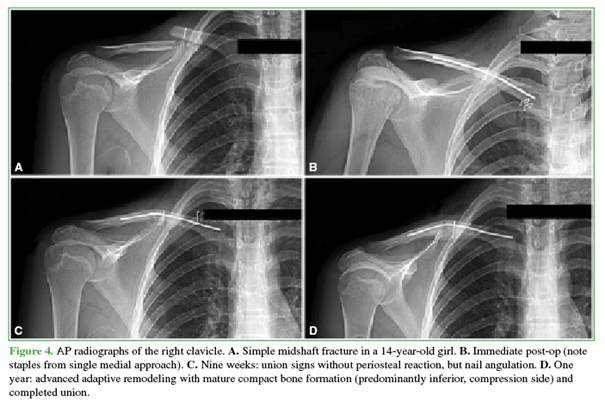

One patient had nail angulation without breakage or other associated complication (Figure 4). Clinical evolution matched the cohort (Constant–Murley: 84 at 6 weeks; 95 at 6 months; 97 at 12 months).

We observed one nail angulation without malunion (angle <30°), delayed union, or nonunion. This occurred because, at the fracture ends, four times of loads are present: axial load, two bending moments (AP and lateral), and torsion. With a single intramedullary nail, typical in the clavicle’s narrow canal, the construct chiefly controls axial load. For this reason, we indicate the use of a sling for 3 weeks (to limit bending) and no forward flexion >90° before week 4 (to limit torsion).